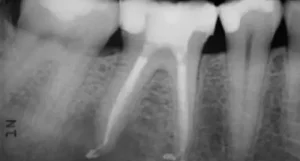

Root canal treatment is a common dental procedure designed to save a severely damaged or infected tooth. It involves removing the infected pulp, cleaning and

Root canal treatment is a common dental procedure aimed at saving a severely damaged or infected tooth. It involves removing the infected pulp, cleaning and